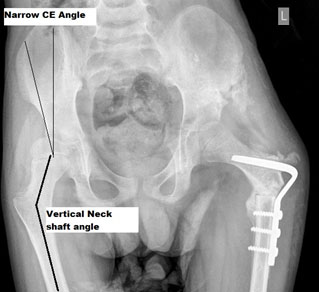

Plain X rays are helpful after the age of 4-6 months when there is ossification of the femoral head physis. Two entities need to be understood- hip dislocation and hip dysplasia. No contact between the femoral head and the acetabular cartilage is a dislocation of the hip. Partial contact between the femoral head and acetabular cartilage but not adequate is hip dysplasia.

HIP DISLOCATION

As shown in the X-ray, the femoral head should be typically in the lower inner quadrant while in a dislocated hip, it is in the upper outer quadrant. The horizontal line that connects the two triradiate cartilage is called Hilgenreiner’s line. The vertical line on the outer margin of the acetabulum that is perpendicular to the above line is called Perkin’s line. There is also a break in Shenton’s line.

HIP DYSPLASIA

It is an entity where there is no adequate lateral and anterior coverage of the hip joint. Dysplasia is measured radiologically by certain angles in the hip joint. It is assessed by taking AP and false profile view of the affected joint. Acetabular index- It is useful after six months of age and is generally less than 25 degrees. It is an angle formed by the triradiate cartilage and the lateral point on the acetabulum. The center-edge (CE) angle of Weiberg – The angle formed by a vertical line from the center of the femoral head with another from the center to the outer margin of the acetabulum.